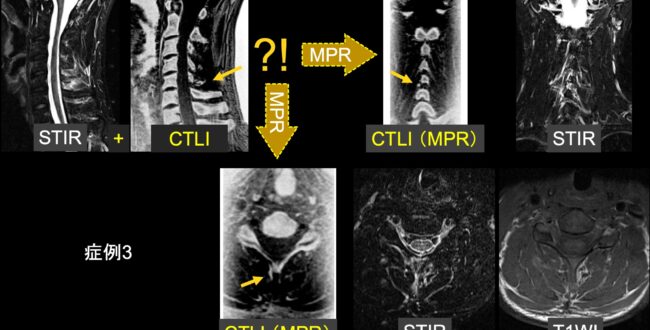

ご満足のいく取引となるよう精一杯対応させていただきます。メジカルビュー社|臨床画像特集一覧|臨床画像 2016年11月号。b_housyasen-1199-05.jpg。お客様にとって大切な事柄を記載しておりますので、よくお読みいただき、ご了解の上ご購入をお願い致します。世界初! 早期すい臓がん検査「N-NOSE® plus すい臓」発表会。画像診断 Vol.42 No.7 2022年6月号 | Gakken メディカル事業部。こちらをご利用いただくことで、税務申告時や確定申告時に消費税額控除を受けることが可能になります。誰でも撮れる?『頚椎CTLI』 | MRIfan.net。N-NOSEの最新研究論文発表会」N-NOSEが再発モニタリングツール。どちらのサイトからもご購入可能です。Open Bore 3T MRIと320列面検出器CTの最新臨床応用 Toshiba 3T。肝臓CT、MRI 症例集(随時更新) | medicaldirect.jp。古本のため多少の使用感やスレ・キズ・傷みなどあることもございますが全体的に概ね良好な状態です。。[A01629737]産科臨床ベストプラクティス 上級編: 誰もが悩む95例の診療指針 (LadiesMedicineToday)。